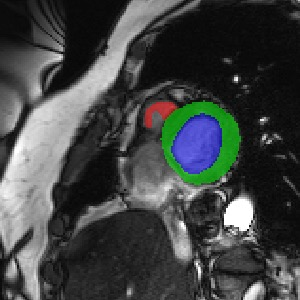

Transformers, the default model of choices in natural language processing, have drawn scant attention from the medical imaging community. Given the ability to exploit long-term dependencies, transformers are promising to help atypical convolutional neural networks (convnets) to overcome its inherent shortcomings of spatial inductive bias. However, most of recently proposed transformer-based segmentation approaches simply treated transformers as assisted modules to help encode global context into convolutional representations without investigating how to optimally combine self-attention (i.e., the core of transformers) with convolution. To address this issue, in this paper, we introduce nnFormer (i.e., Not-aNother transFormer), a powerful segmentation model with an interleaved architecture based on empirical combination of self-attention and convolution. In practice, nnFormer learns volumetric representations from 3D local volumes. Compared to the naive voxel-level self-attention implementation, such volume-based operations help to reduce the computational complexity by approximate 98% and 99.5% on Synapse and ACDC datasets, respectively. In comparison to prior-art network configurations, nnFormer achieves tremendous improvements over previous transformer-based methods on two commonly used datasets Synapse and ACDC. For instance, nnFormer outperforms Swin-UNet by over 7 percents on Synapse. Even when compared to nnUNet, currently the best performing fully-convolutional medical segmentation network, nnFormer still provides slightly better performance on Synapse and ACDC.